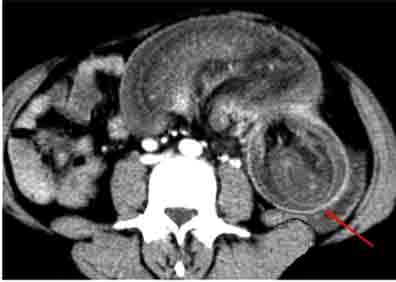

| Hernie inguinale etranglee : Image TDM en

coupe axiale a travers L5 |

Hernie

inguinale etranglee : Meme cas en coupe axiale a

travers symphyse pulbienne |